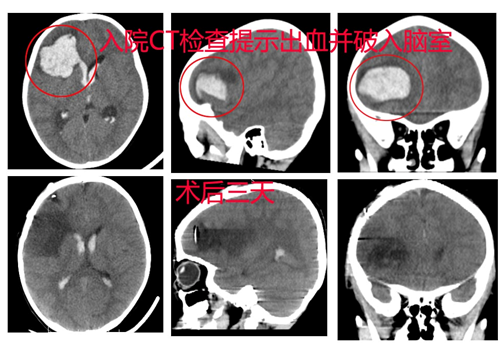

病例1 额叶动静脉畸形

患者曹某,男,3岁,因“突发头痛、呕吐3小时”于2016-02-20入院;专科检查: 昏迷,不能睁眼,不能发音,刺痛躲避。双侧瞳孔等大等圆,直径2.0mm,对光反射灵敏;辅助检查:头颅CT提示:右额叶脑出血并破入脑室、脑积水、脑肿胀。入院后完善CTA检查,急诊手术治疗。术程顺利,术后患者恢复良好。